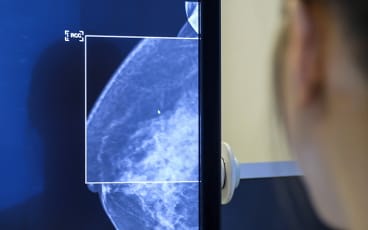

• Mammografi, ibland kompletterad med ultraljud.

Yngre kvinnor har tätare bröst, det vill säga mer bröstkörtelvävnad än äldre, vilket gör det svårare att på mammografibilder se eventuella förändringar.

Därför kompletteras mammografin med ultraljud. Ultraljud kan inte ersätta mammografi men är ett bra komplement för att undersöka brösten framförallt på yngre kvinnor.